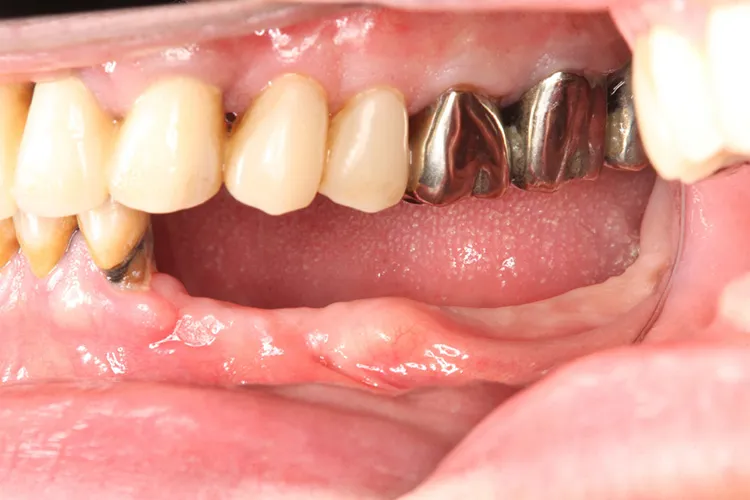

症例3/

左下5本欠損した部分をインプラント3本埋入して5本ブリッジで治したケースです。なかなかインプラントに踏み切れず、長い間入れ歯を使っておられましたが、噛みごたえがなく好きなものが食べれない上に、度々歯茎が痛んでは調整の繰り返しで快適に過ごすことができず、QOLの向上のためインプラント治療を決断されました。今ではなんでも食べれるとのことで、入れ歯で我慢しないでもっと早くインプラントにすればよかったと言っておられます。